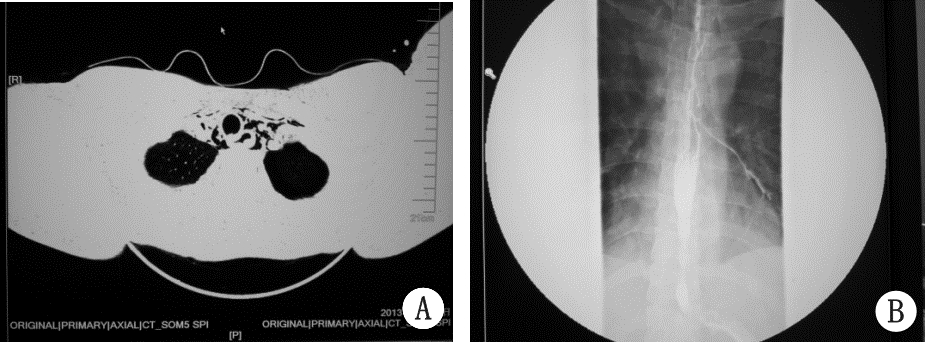

患者男性,31岁,化验室实验员,工作过程中可接触氯化汞。因“上腹痛17 h,呕血,黑便,无尿11 h”入院。患者入院前17 h误服氯化汞10 g,服后约0.5 h出现上腹痛,6 h后开始呕吐新鲜血及排黑便,并逐渐出现无尿。入院时查体:T 37.5 ℃,P 96 次/min,R 26次/min,BP 118/83 mmHg(1 mmHg=0.133 kPa),烦躁,口腔内可见鲜红色液体,触诊颈部及前胸部有握雪感,双肺未闻及干湿啰音,腹软,上腹部压痛,无反跳痛及肌紧张,肠鸣音3 次/min。 入院辅助检查:胸腹部CT(图 1A)示锁骨下、纵隔气肿,左侧气胸,心脏前下方及后下纵膈食管旁可见多发游离气体影,胃壁弥漫性增厚,胃周脂肪密度模糊,肝周、脾周少量积液。血常规:白细胞计数40.4×109 L-1,中性粒细胞百分数91.5%,血红蛋白201 g/L,血小板计数120×109 L-1;生化指标:钾6.52 mmol/L,尿素氮10.63 mmol/L,肌酐292 μmol/L,丙氨酸氨基转移酶76 U/L,天冬氨酸氨基转移酶717 U/L,总胆红素79.4 mmol/L,非结合胆红素47 mmol/L,肌酸激酶526 U/L,肌酸激酶同功酶94 U/L,乳酸脱氢酶7 885 U/L,淀粉酶390 U/L,脂肪酶1 588 U/L; 血气分析:pH 7.318,PCO2 24 mmHg,PO2 136 mmHg,BE-12.1 mmol/L,HCO3-15.4 mmol/L,Lac 4.3 mmol/L。入院诊断:重度氯化汞中毒、消化道出血、腐蚀性食管炎,纵隔气肿、左侧气胸、急性胰腺炎、代谢性酸中毒、高钾血症、高乳酸血症。多器官功能障碍综合征:急性肾损伤3期、急性肝损伤、急性心肌损伤 。治疗经过:患者数字胃肠钡餐透视(图 1B)示食管气管交通。监测血液、血滤废液、尿液汞含量(表 1),患者入院后立即禁食水、肠外营养,抗生素覆盖革兰氏阴性阳性细菌控制感染,质子泵抑制剂抑酸,血液滤过及药物清除炎症介质治疗,营养心肌、保肝等支持治疗。行持续血液滤过治疗急性肾损伤及驱汞,患者见尿后二巯基丙磺酸钠肌注驱汞治疗。经治疗6周后患者痊愈出院

| A:患者入院胸腹部CT结果;B:患者数字胃肠钡餐透视影像 图 1 患者影像学检查结果 |